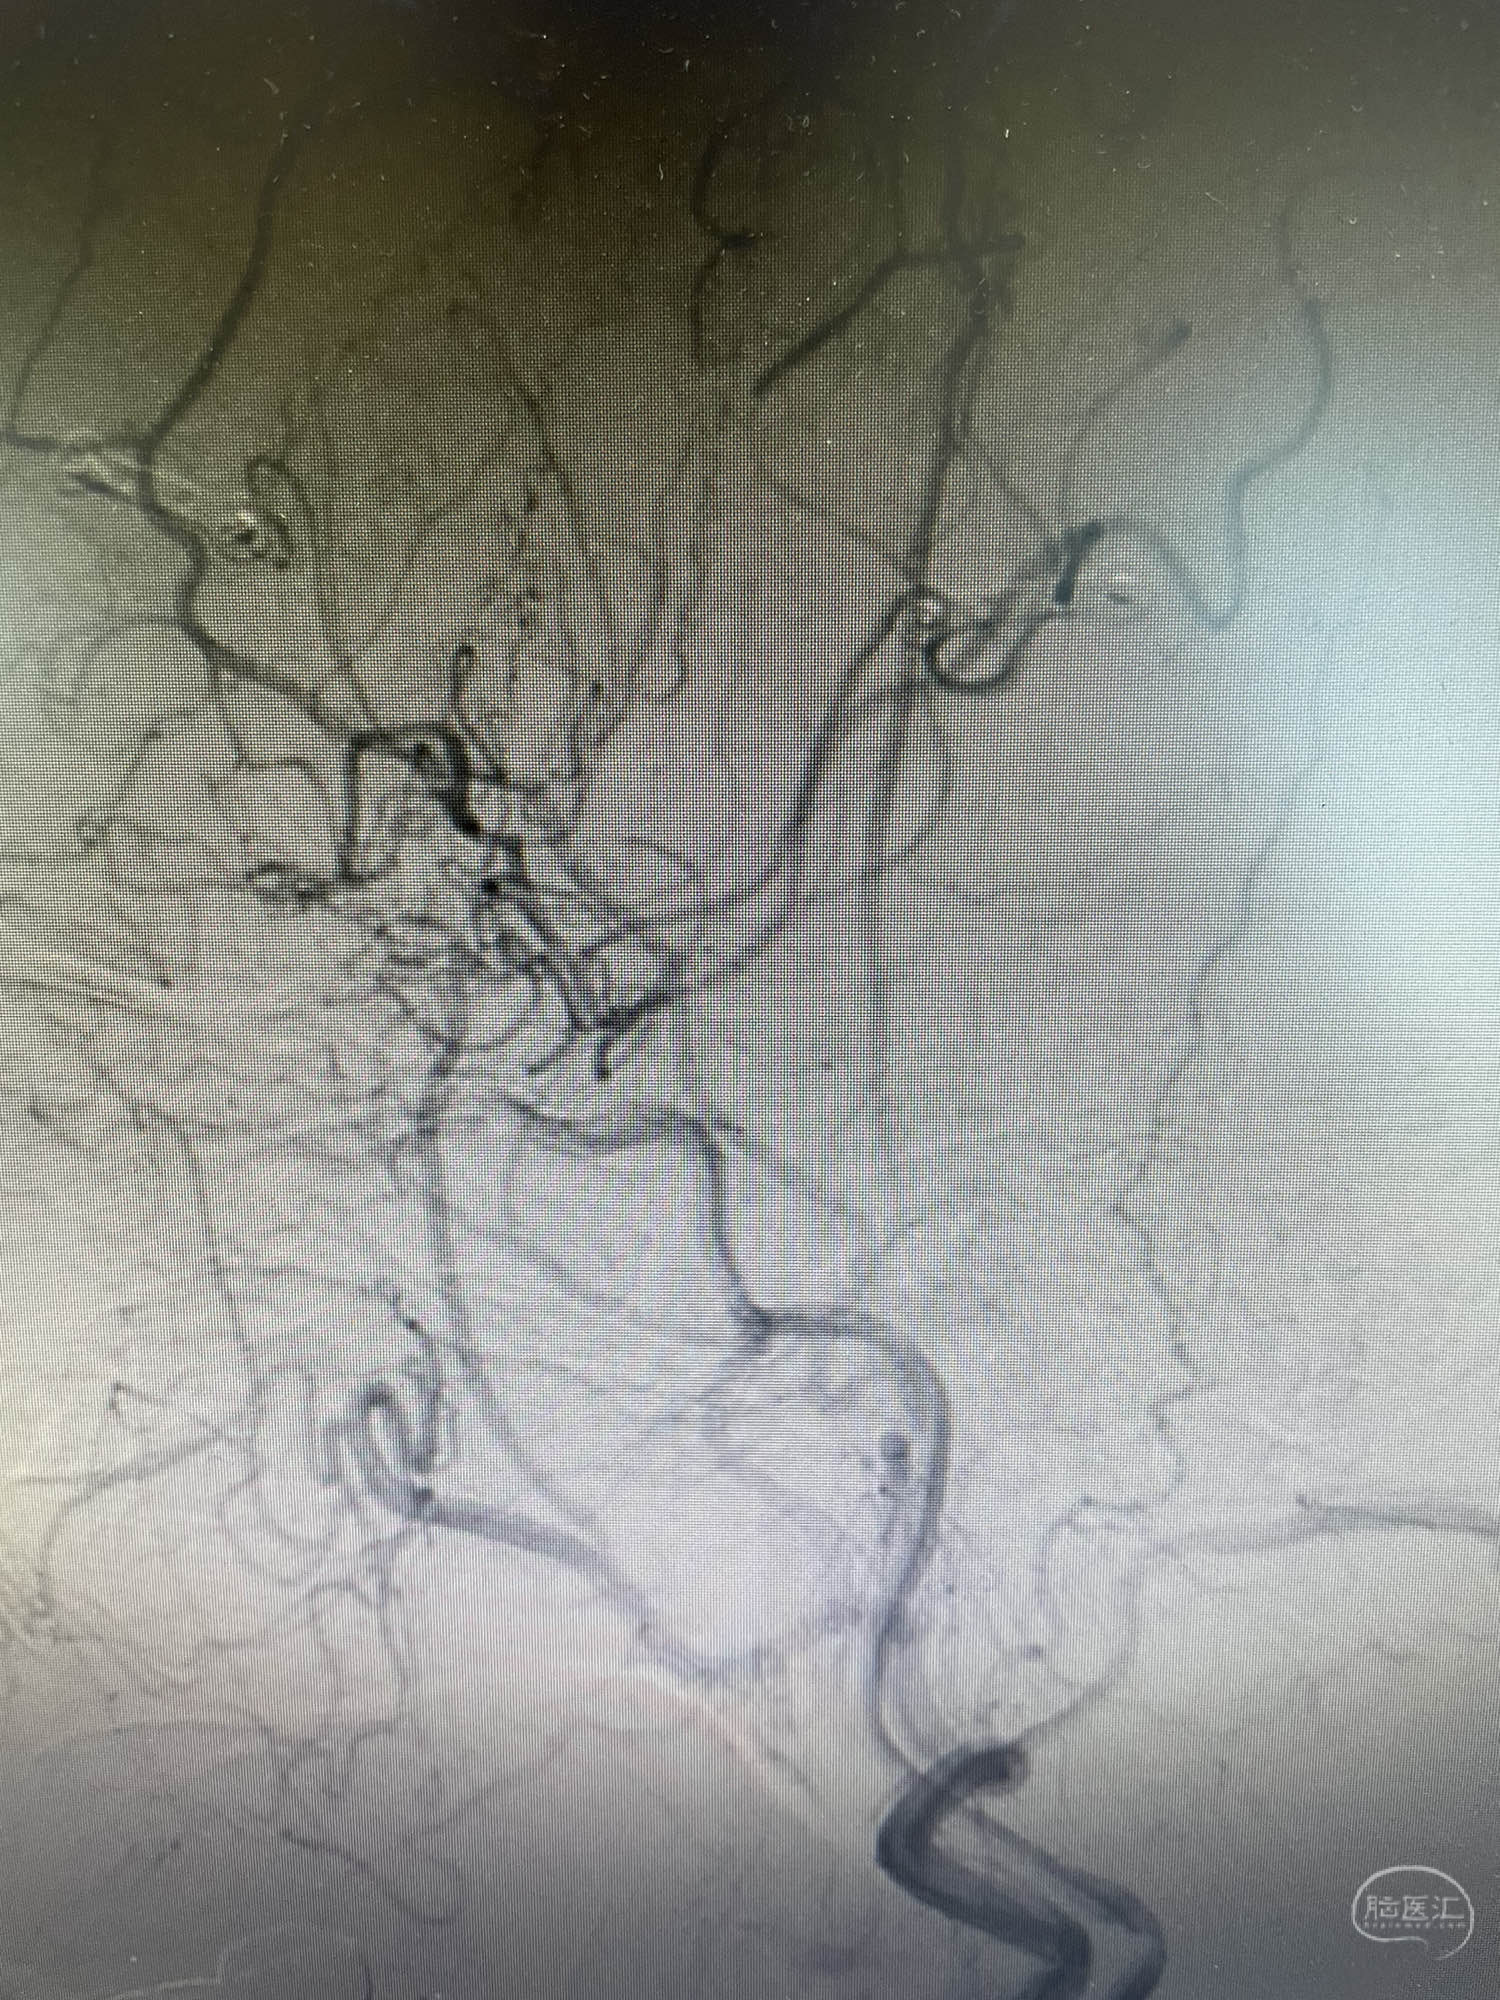

术前片子显示大脑中动脉闭塞